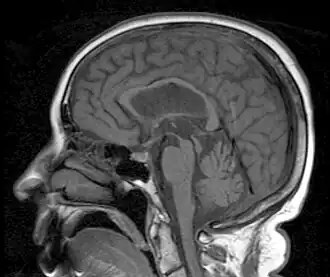

| MRI demonstrating the hummingbird sign of supranuclear palsy due to atrophy of the midbrain | |

Magnetic resonance imaging (MRI) is often used to diagnose PSP. MRI may show atrophy in the midbrain with preservation of the pons giving a "hummingbird" sign.[3][40]

The "humming-bird" imaging feature, indicative of midbrain degeneration, supports early diagnosis of both PSP-RS and PSP-P.[4][49] One commonly used quantitative measure is the midbrain-to-pons area ratio, which is calculated by measuring the cross-sectional areas of the midbrain and pons on midsagittal MRI images.[14]In healthy individuals, the midbrain and pons are proportionally sized, but in PSP-RS, the midbrain undergoes significant atrophy while the pons remains relatively spared.[14][13][49][50] As a result, the ratio is markedly reduced in PSP-RS, distinguishing it from other neurodegenerative conditions such as Parkinson’s disease, multiple system atrophy (MSA), and even PSP-P, which typically exhibit less pronounced midbrain atrophy.[14][13][49][50] To improve diagnostic specificity, the magnetic resonance parkinsonism index (MRPI) incorporates the midbrain-to-pons area ratio along with measurements of the widths of the middle and superior cerebellar peduncles.[14] The MRPI has been shown to enhance discrimination between PSP-RS and other forms of atypical parkinsonism.[14] Additional MRI findings associated with PSP-RS may include third ventricle enlargement, thinning of the superior cerebellar peduncles, and frontal lobe atrophy, all of which are consistent with the underlying tau pathology seen in the disease.[14] Brain atrophy in PSP-RS is generally symmetrical, which may correspond to the bilateral presentation of motor and cognitive symptoms.[17]